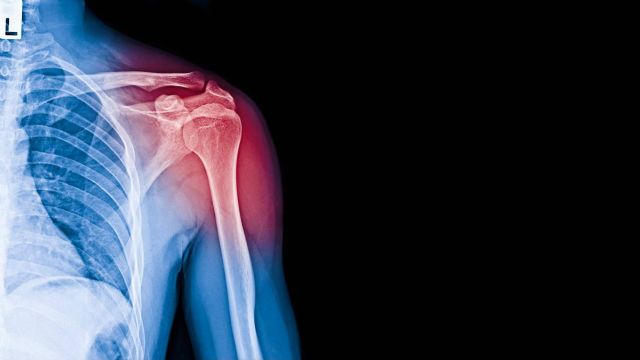

Se trata de una afección que cursa con dolor e involucra la inflamación del tendón del músculo supraespinoso que, junto con los músculos infraespinoso, redondo menor y subescapular, forma parte del denominado manguito de los rotadores que aporta estabilidad y desempeña un papel fundamental, tanto en la elevación como en la rotación del brazo.

La tendinopatía del supraespinoso es una inflamación acompañada de irritación que se desarrolla en el tendón por excelencia de la articulación del hombro (músculo supraespinoso). Esta lesión es característica principalmente en aquellas personas que realizan actividades laborales o deportivas con un uso excesivo de movimientos repetitivos del brazo por encima de la cabeza, los cuales originan una tendinitis por desgaste y fricción de la zona.

El traumatólogo de Bilbao utiliza un método para determinar la tendinitis de supraespinoso con preguntas previas que involucran a la rutina diaria, la historia clínica y las sintomatologías del paciente. Una vez obtenidos todos estos datos, el especialista efectúa una exhaustiva exploración física que verifica la amplitud de movimiento, estabilidad, fuerza y sensibilidad del hombro; para luego proceder a pruebas de diagnóstico por imágenes como radiografías, resonancias magnéticas y ecografías.